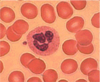

leukocytosis (granulocytosis) - Chronic Myelogenous Leukemia

Leukocytosis (Granulocytosis) – Chronic Myelogenous Leukemia